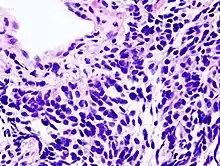

Micrograph of a small-cell carcinoma of the lung showing cells with nuclear moulding, minimal amount of cytoplasm and stippled chromatin. FNA specimen. Field stain.